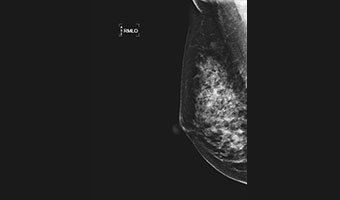

全乳覆盖高效检查

低剂量高清图像

微小病灶,清晰呈现

24×30cm大面积成像,

放大摄影功能,微小病灶无处遁形

低剂量高清晰兼顾

进口钼靶球管 X射线更适合乳腺检查 管球寿命更高 钼铑双滤过,根据乳房致密度自动智选